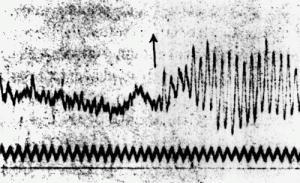

Estas son las ondas cerebrales de la hija de 14 años de Berger mientras calculaba 196 entre siete. El científico alemán reunió más de 1.000 lecturas similares antes de anunciar al mundo que había descubierto el electroencefalograma humano en 1929.